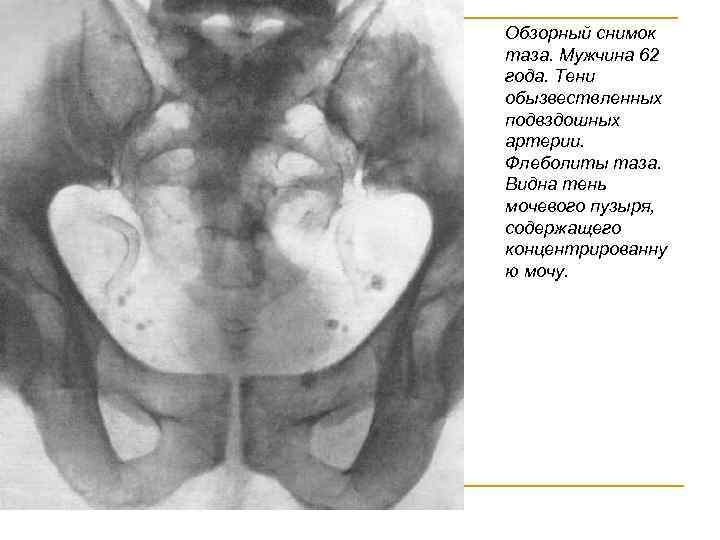

Нормальные мочеточники на обзорном снимке не видны. Тень мочевого пузыря может быть выявлена, если последний наполнен насыщенной мочой. Нормальный мочевой пузырь на обзорном снимке имеет форму эллипса. После того как на рентгенограмме рассмотрены костная система, тени почек и мочевых путей, обращают внимание на возможное наличие добавочных теней. Добавочные, т. е. ненормальные, тени могут быть самыми разнообразными и относиться к различным органам и тканям: коже, органам брюшной полости, забрюшинного пространства, костям и т. д. Любая тень, имеющая ту или иную степень плотности и находящаяся в зоне расположения мочевых путей, должна трактоваться как тень, возможно имеющая отношение к мочевым путям ( “тень, подозрительная на конкремент”).

Обзорный снимок таза. Мужчина 62 года. Тени обызвествленных подвздошных артерии. Флеболиты таза. Видна тень мочевого пузыря, содержащего концентрированну ю мочу.